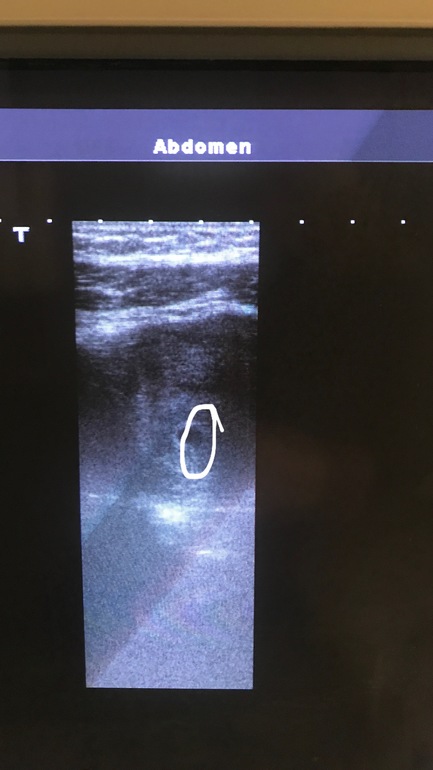

По поводу снимка узи

УЗИ, КТГ, доплерЯ тут пересматриваю узи своё и вот что мне интересно. Я сейчас скину 3 фотки. Оригинал и 2 с обведёнными кругами. Я присмотрелась и такое чувство, будто бы там как перегородка что-ли. Ну в общем посмотрите. Вот плодное яйцо более темное и сбоку как что-то круглое, но не такое тёмное. Что это?))